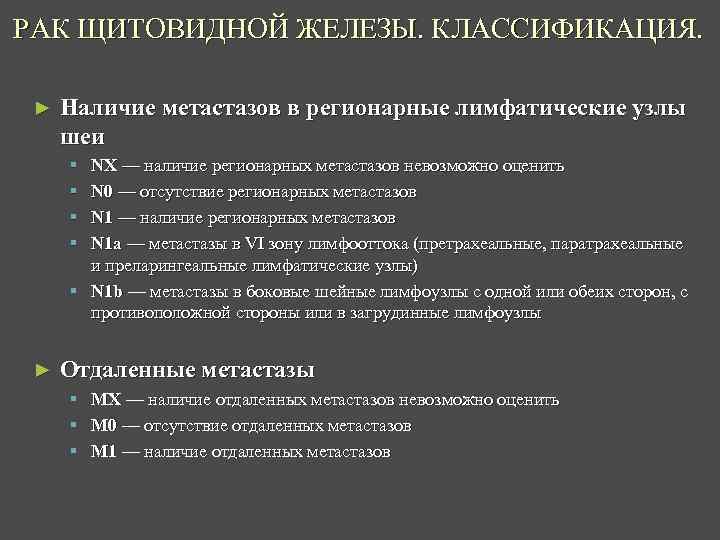

РАК ЩИТОВИДНОЙ ЖЕЛЕЗЫ. КЛАССИФИКАЦИЯ. ► Наличие метастазов в регионарные лимфатические узлы шеи § § NX — наличие регионарных метастазов невозможно оценить N 0 — отсутствие регионарных метастазов N 1 — наличие регионарных метастазов N 1 a — метастазы в VI зону лимфооттока (претрахеальные, паратрахеальные и преларингеальные лимфатические узлы) § N 1 b — метастазы в боковые шейные лимфоузлы с одной или обеих сторон, с противоположной стороны или в загрудинные лимфоузлы ► Отдаленные метастазы § MX — наличие отдаленных метастазов невозможно оценить § M 0 — отсутствие отдаленных метастазов § M 1 — наличие отдаленных метастазов